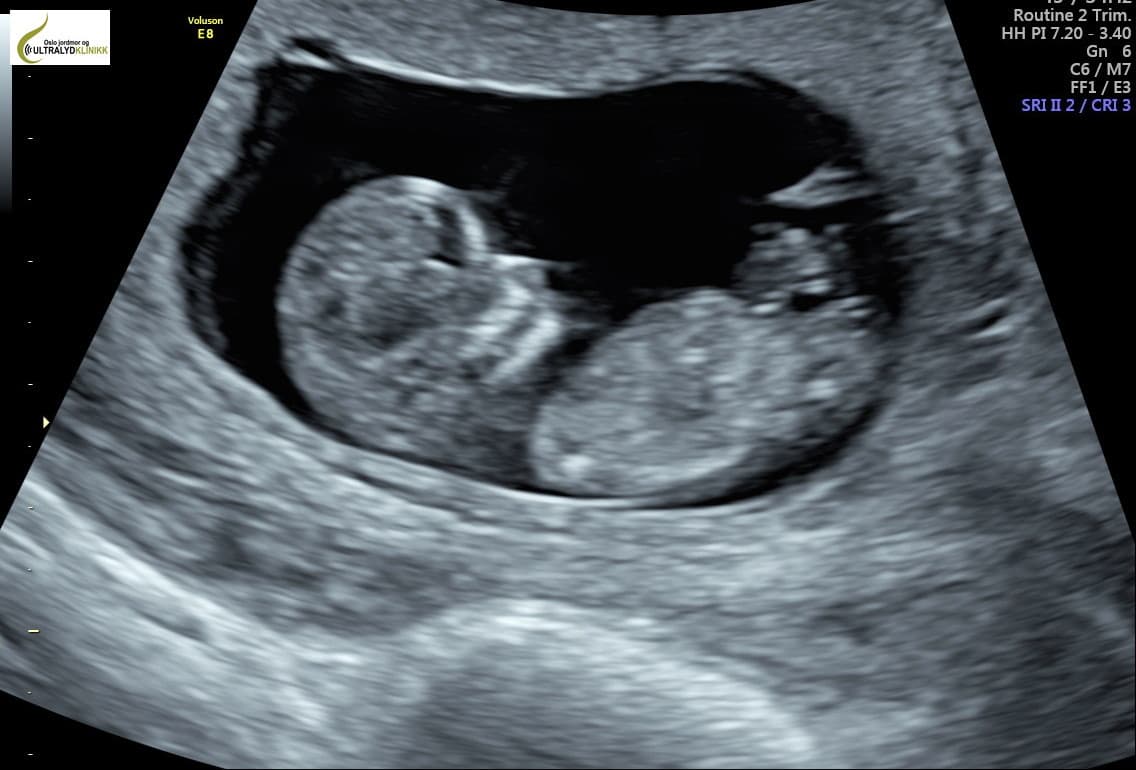

Fra og med idag må alle gravide kvinner i Ungarn som ønsker abort, høre på fosterets hjerterytme før de bestemmer seg for å abortere barnet eller ikke.